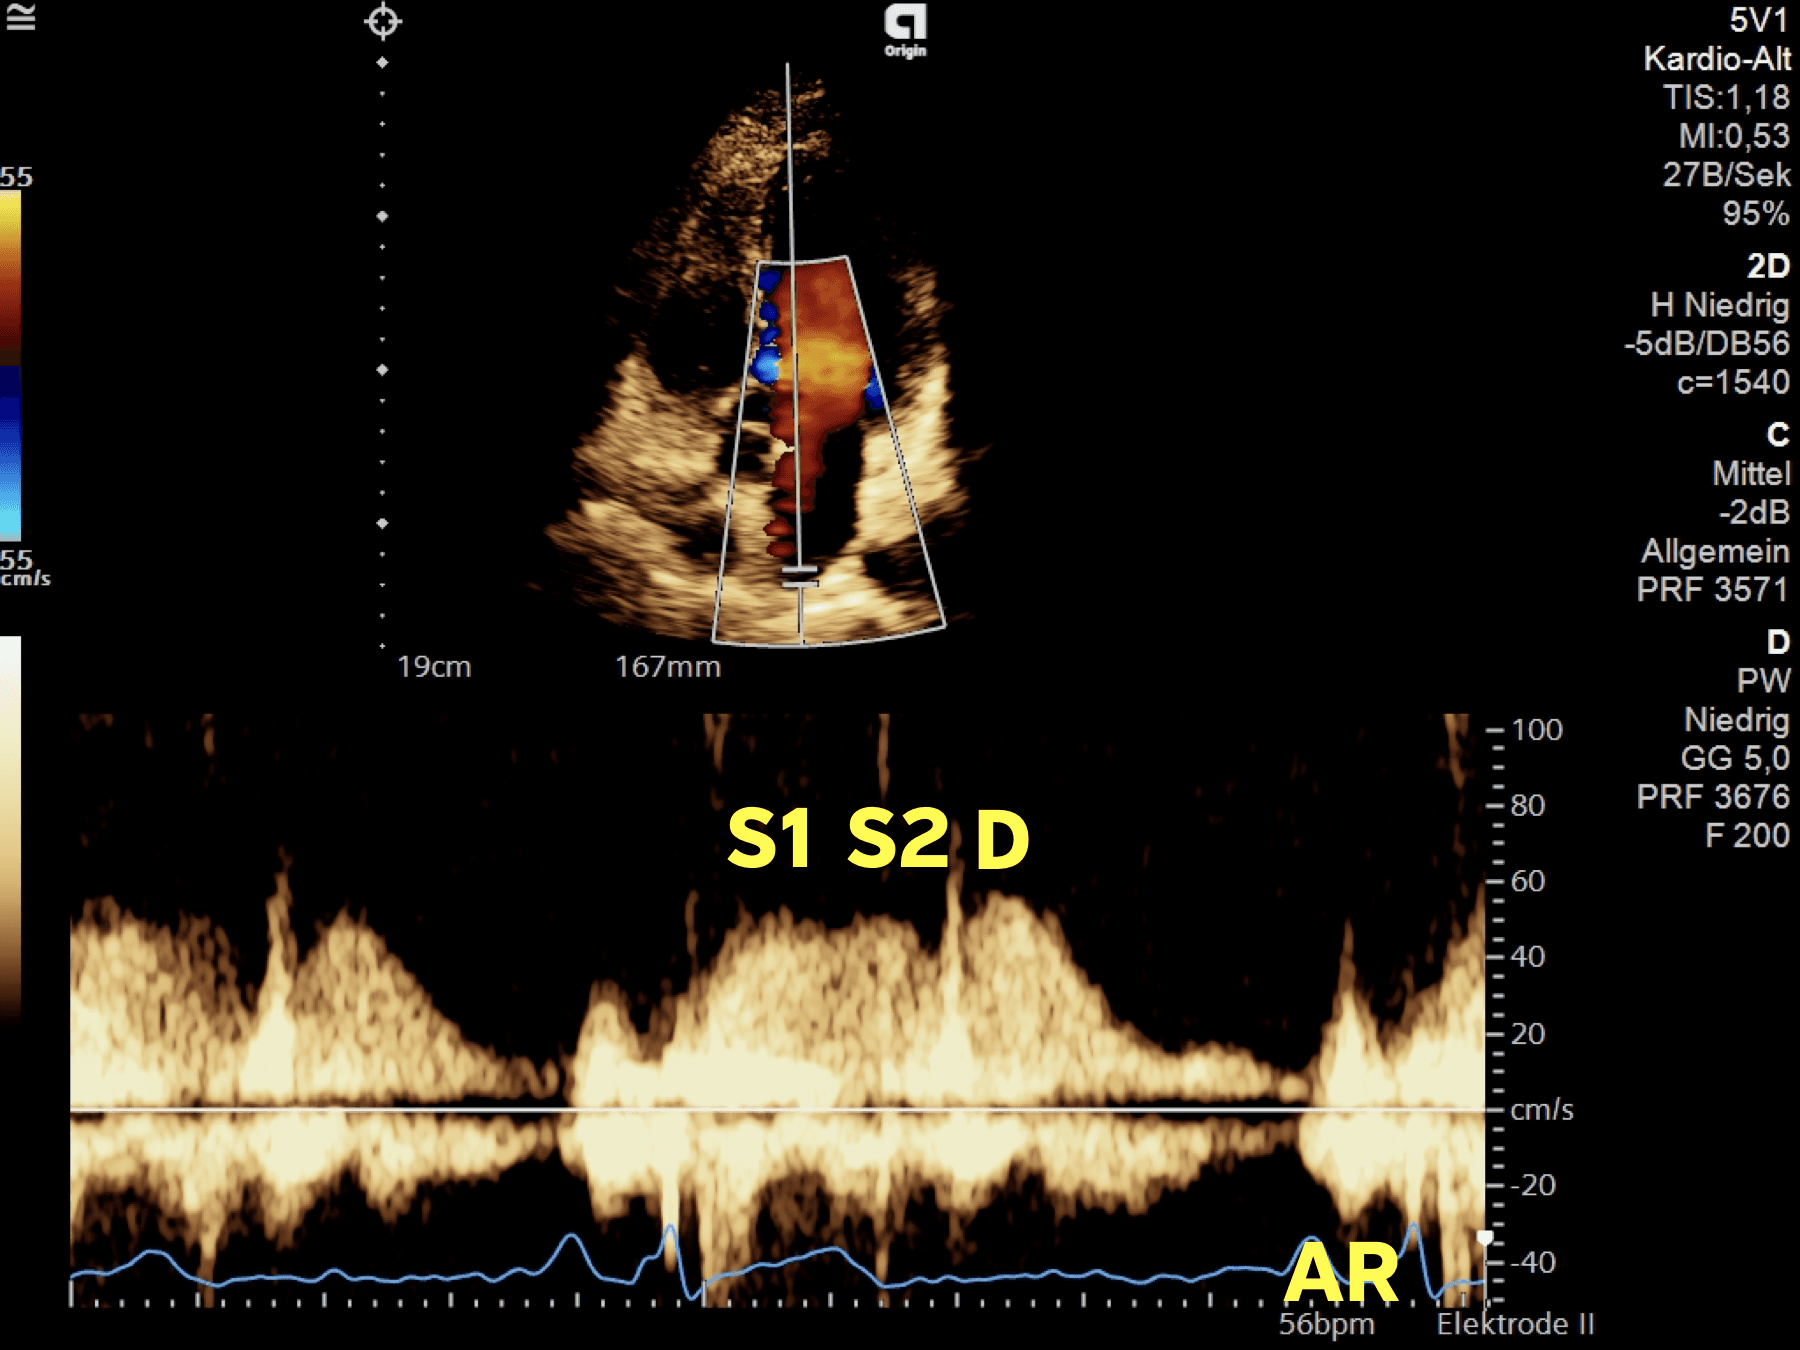

LA reservoir takes place during LV contraction (systole). During LV systole, an elastic recoil after the LA contraction leads to an expansion of the LA dimensions & to a reduction of the LAP. Blood is sucked in from the PV (PV signal S1)

Elevation in the LA dimensions leads to a decline in LAP. The RV systolic pressures are simultaneously measurable at this time period (translation of the pressures) ➜ blood flows into the LA (S2 PV signal)

This calculation ignores the insignificant back-flow volume of the pulmonary veins (no real measurement possible in echocardiography — AR is small)

LAScd = D-wave (PV)

A small shift of volume back to the PV is seen in healthy individuals as well (Ar)